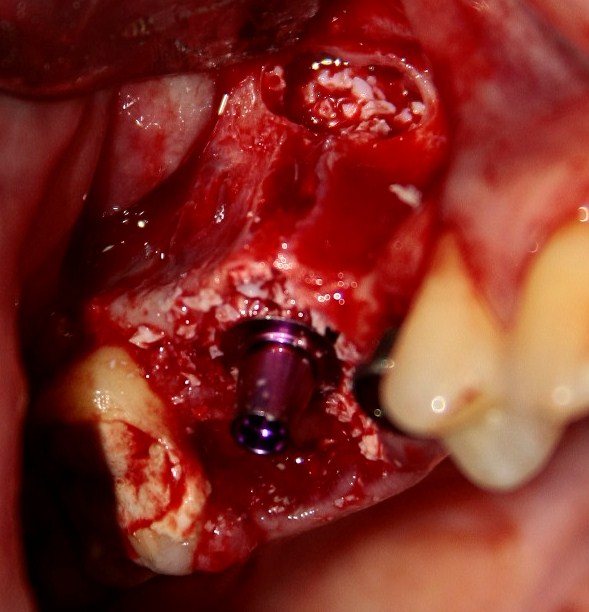

Немедленная имплантация — оптимальное решение в любой клинической ситуации